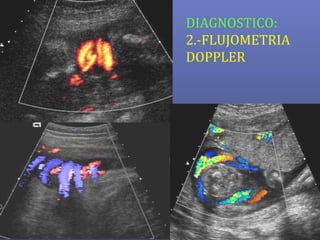

DIAGNOSTICO:

2.-FLUJOMETRIA

DOPPLER

 Compartimiento Materno

 Compartimiento Fetal

 Compartimiento

Placentario

Art. UterinasArt. Uterinas

Art. UmbilicalArt. Umbilical

o Art. Cerebral MediaArt. Cerebral Media

o Ductus VenosoDuctus Venoso